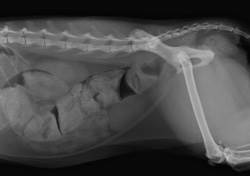

Диагностика

Иногда причину запора удается установить уже при осмотре. Обычно требуется проведение стандартного набора диагностических мероприятий: общий и биохимический анализы крови, иногда – анализ мочи, УЗИ внутренних органов, иногда – рентген с применением контраста. При подозрении на заболевания толстого отдела кишечника проводится колоноскопия.